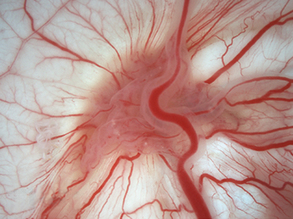

Inflaming Hearts